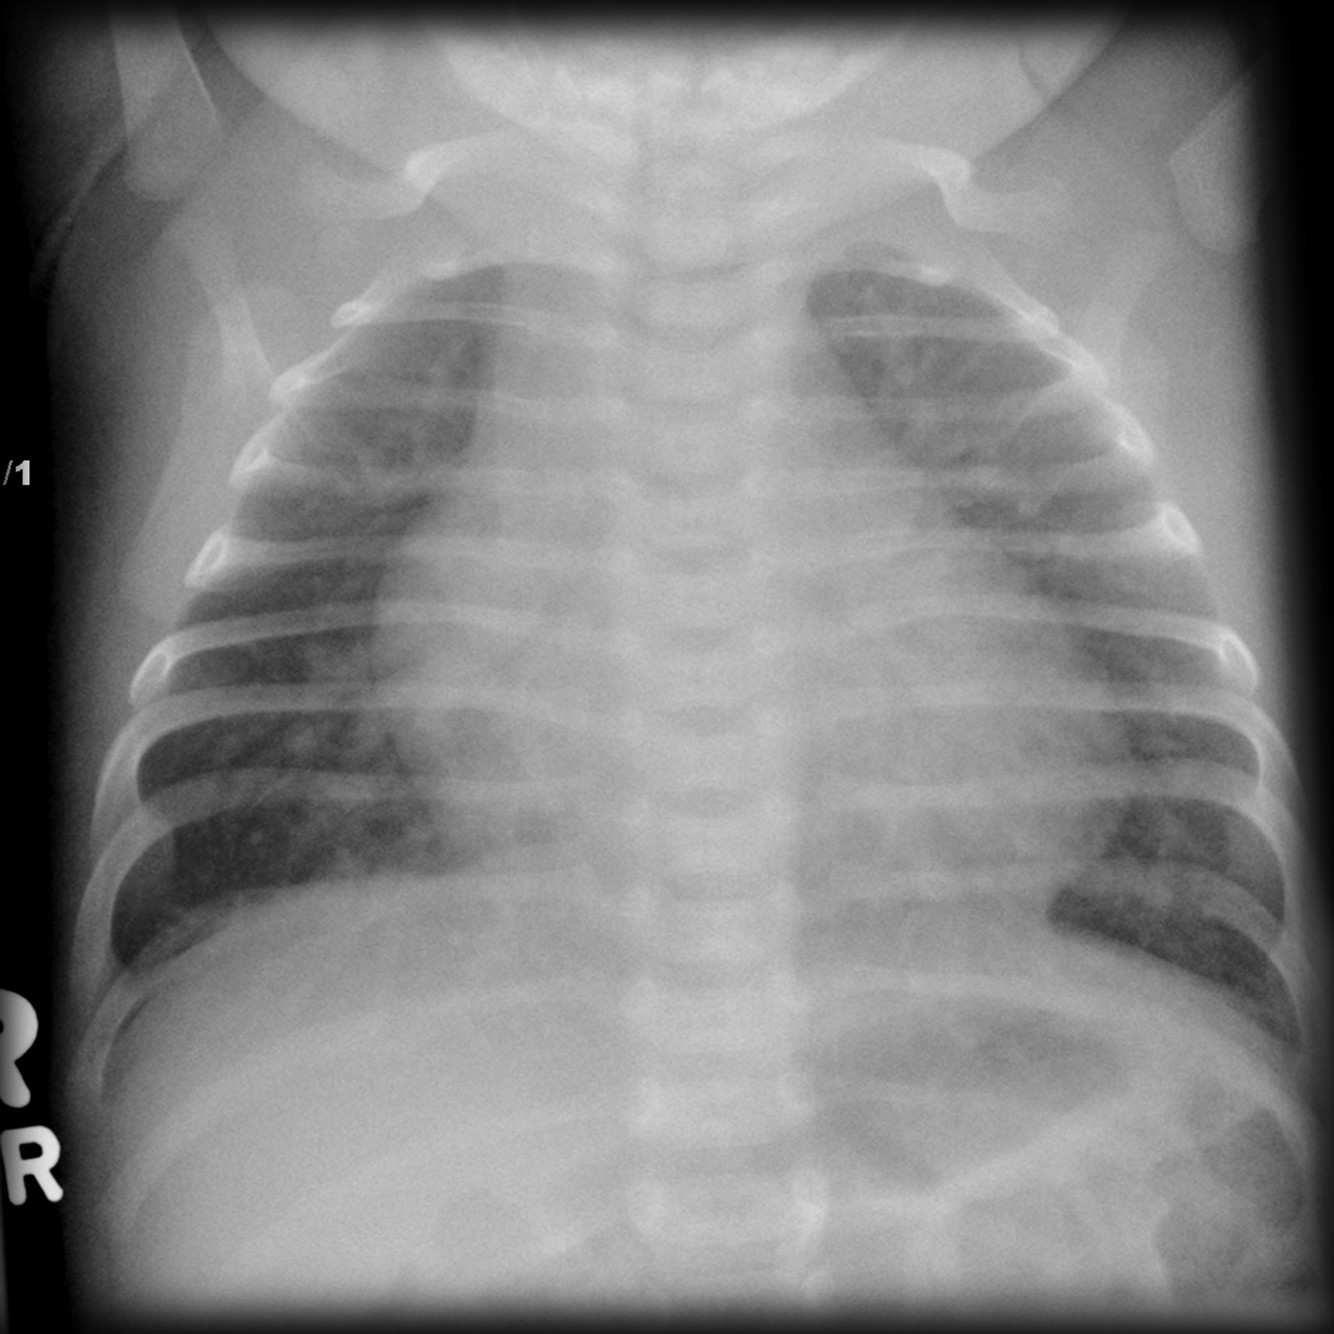

Plain radiograph

The chest radiograph can be normal with a small VSD. Larger VSDs may show cardiomegaly (particularly left atrial enlargement although the right and left ventricle can also be enlarged). A large VSD may also show features of pulmonary arterial hypertension, pulmonary oedema, pleural effusion, and increased pulmonary vascular markings.

Cyanosis: there are no definitive signs to predict cyanosis by plain radiograph however, as a rule of thumb, cyanotic patients (right-to-left shunt) have small PAs, and the main PA segment may not be visible or is concave.